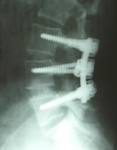

The problem is that back pain is a gait issue (an issue with the way you walk).  If your gait is irregular enough, you will get back pain, may have disc problems and are a likely candidate for sciatica  or sacro iliac problems and will not be flexible.  If you were unlucky enough to be sent directly to a surgeon because of your level of pain, you may make that rash decision for a surgery that is harmful rather than helpful because if does not correct the way you walk and instead, attempts to put stability in an area that is being torn apart by the way you walk.

In our office, we prevent many people from ever needing back surgery. The few who do are chosen well and generally do much better than they did prior.  The secret to successful back surgery is picking the person properly.